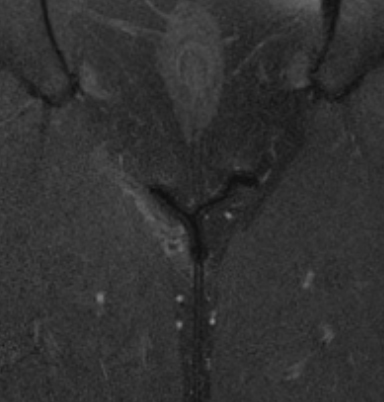

Nun habe ich mir die MRT-Bilder selber angeschaut und bin der festen Meinung, dass genau in dem Bereich wo ich Probleme habe, eine deutliche Auffälligkeit im Vergleich zum anderen Bein zu sehen ist. Diese hellere Struktur ist wohlgemerkt nicht nur in einer Schicht der Aufnahme zu sehen, sondern auf 14.

Anbei einmal zwei Unterschiedliche Sequenzen. Das schwarze Y was ihr seht ist der Bereich linkes Bein/rechtes Bein, oben Genitalbereich. Links ist eine deutliche hellere Struktur zu erkennen als rechts (Adduktoren).